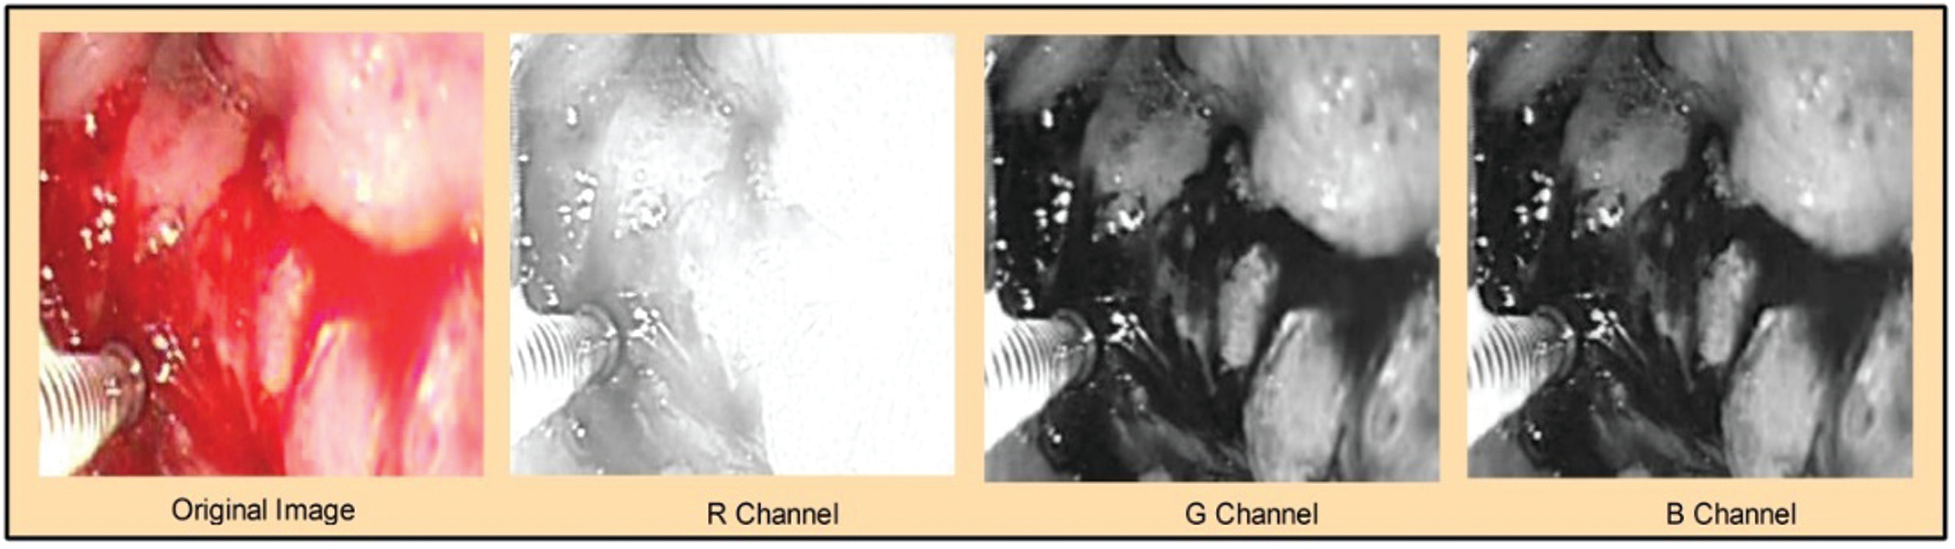

Figure 2: Visualization of the original image and extracted channels:

Considering three channels